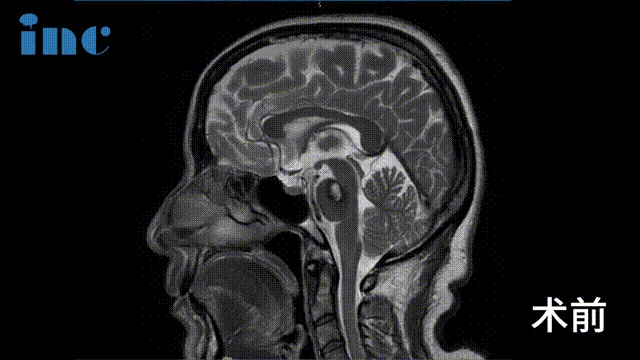

▼術(shù)前及術(shù)后1天影像對比

術(shù)前及術(shù)后1天影像對比